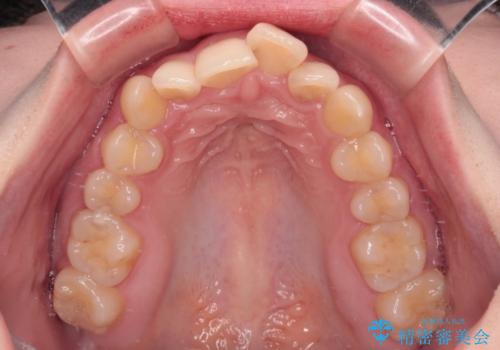

- デコボコになっている前歯を気にして来院された患者様です。

口元の突出感は気になっていないものの、デコボコを解消すると口元が前方に突出する可能性があるため、上下左右の第一小臼歯4本を抜歯して、ワイヤー装置にて矯正治療を行うこととしました。

下の前歯が隠れてしまうほど深く咬みこんでいたため、上顎前歯が前方に突出しているような印象がありましたが、咬み合わせが改善され、整った口元に仕上げることができました。